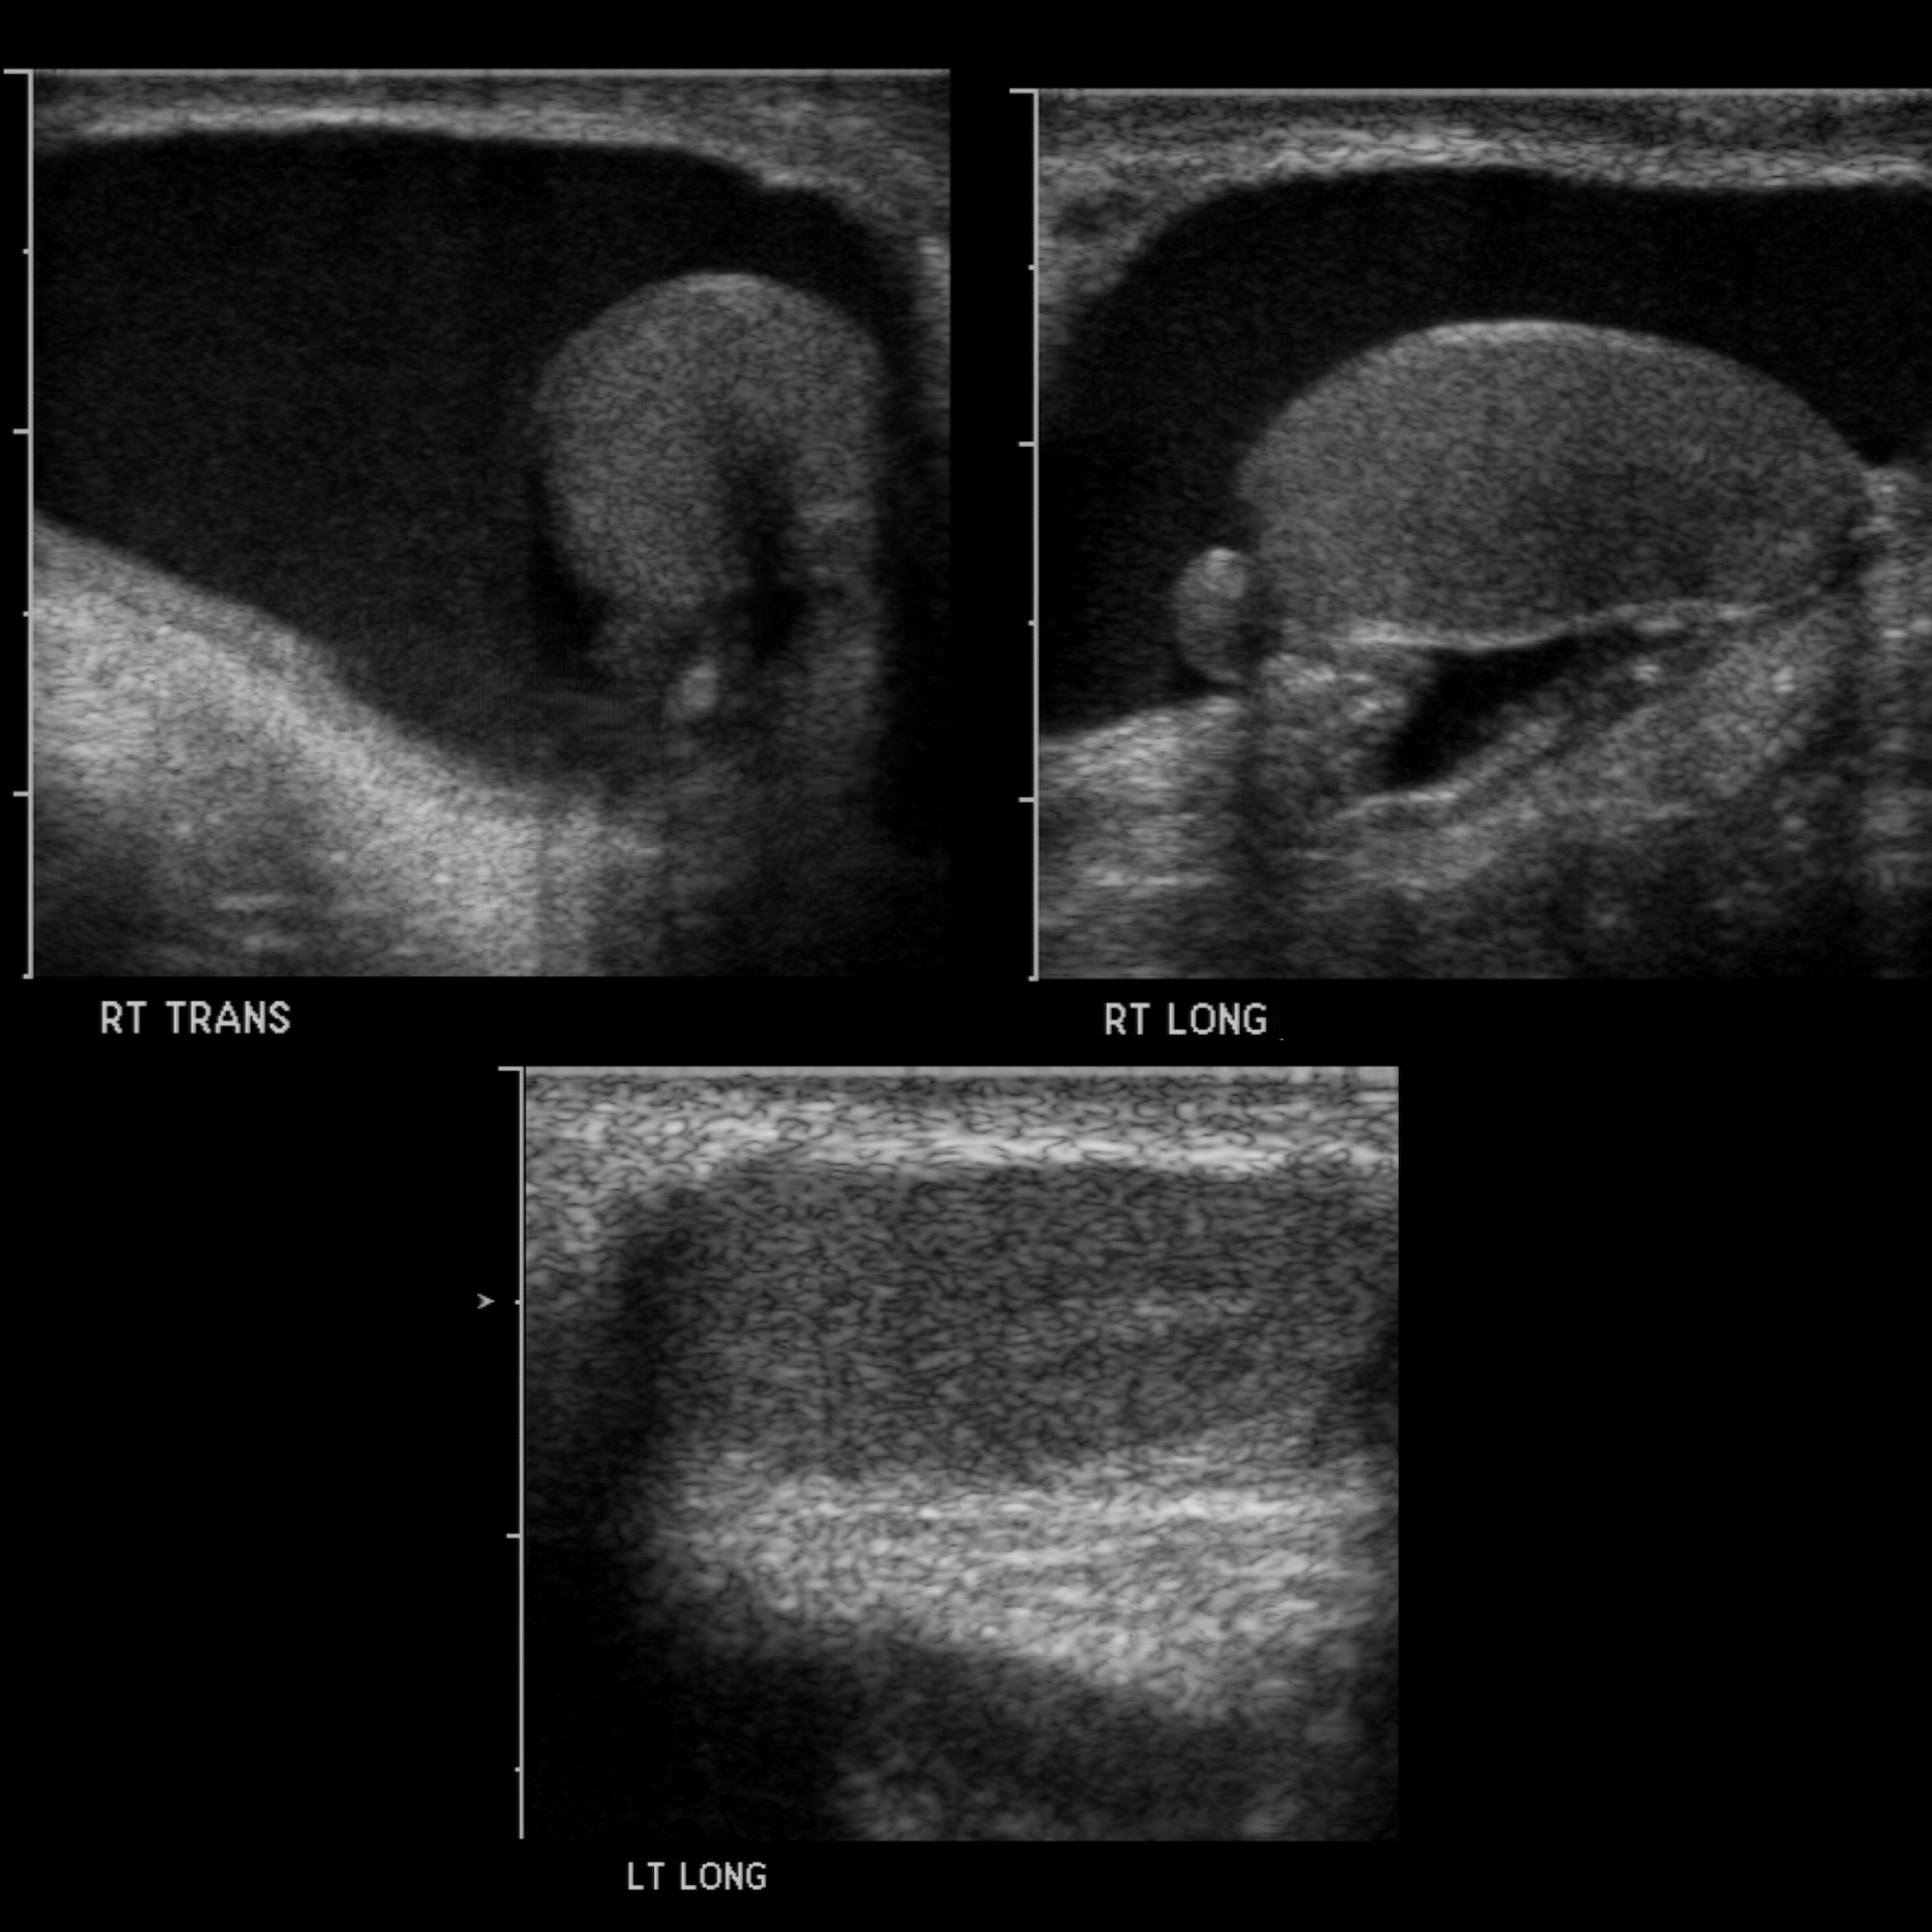

COMPLEX HYDROCELE Looking Through a Transducer Drainage Hydrocele Cpt Cpt code 55041 should be used when the provider performs a bilateral excision of hydrocele from both sides of the scrotum. After institutional review board approval and informed consent were obtained, patients from a single provider's men's health specialty practice were retrospectively identified by billing diagnosis code for hydrocele or spermatocele (cpt code n43.3 or n43.4, respectively) from october 1,. Drainage Hydrocele Cpt.